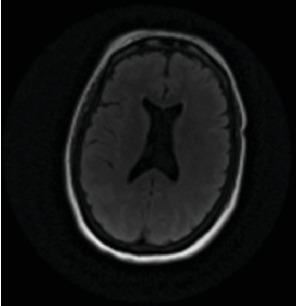

迟发性缺氧后白质脑病(DPHL)是一种罕见的诊断,可能与其他更常见的神经系统疾病(如紧张症)相似。虽然一氧化碳中毒很常见,但也可能是由于其他原因引起的缺氧,如药物过量或心脏骤停。由于其症状的迟发性和与其他疾病的重叠,最初可能被误诊。我们报告一名50岁女性患者,有抑郁史,在家中发现无反应、缺氧和发热,时间不详。最初担心的是败血症。最初的头部计算机断层扫描(CT)和脑部磁共振成像(MRI)正常。患者有横纹肌溶解伴继发性肾衰竭、肝休克和急性胰腺炎。药物稳定后,她的认知能力恢复到正常基线。然而,在住院10天后,她的精神状态恶化,表现为沉默、麻木、凝视、口服摄入量减少和毅力。怀疑继发于重度抑郁发作的紧张症。劳拉西泮向上滴定无结果。劳拉西泮无反应提示再次进行脑部MRI检查,显示双脑额叶、颞叶、顶叶和枕叶弥漫性白质改变。诊断为DPHL。随后,她开始服用卡比多巴/左旋多巴25/100 mg,情况有所改善,并出院至康复机构。

Delayed posthypoxic leukoencephalopathy (DPHL) is a rare diagnosis that may present similarly to other more common neurological conditions, such as catatonia. While often seen with carbon-monoxide poisoning, it can also be due to anoxia due to other causes, such as drug overdose or cardiac arrest. Due to the delayed nature of its symptoms and overlap with other conditions, it can be initially misdiagnosed. We present a 50-year-old female patient with a history of depression who was found unresponsive, hypoxic, and febrile at her home for an unknown amount of time. The initial concern was for sepsis. Initial computed tomography (CT) of the head and magnetic resonance imaging (MRI) of the brain were normal. The patient had rhabdomyolysis with secondary renal failure, shock liver, and acute pancreatitis. Once medically stabilized, her cognition returned to a normal baseline. However, 10 days into her hospitalization, her mental state deteriorated, displaying symptoms of mutism, stupor, staring, decreased oral intake, and perseveration. Catatonia, secondary to a major depressive episode, was suspected. Lorazepam was titrated upward without result. Lack of response to lorazepam prompted a repeat brain MRI, revealing diffuse white matter changes in the frontal, temporal, parietal, and occipital lobes of both hemispheres. A diagnosis of DPHL was made. She was then started on carbidopa/levodopa 25/100 mg with improvement and was discharged to a rehabilitation facility.